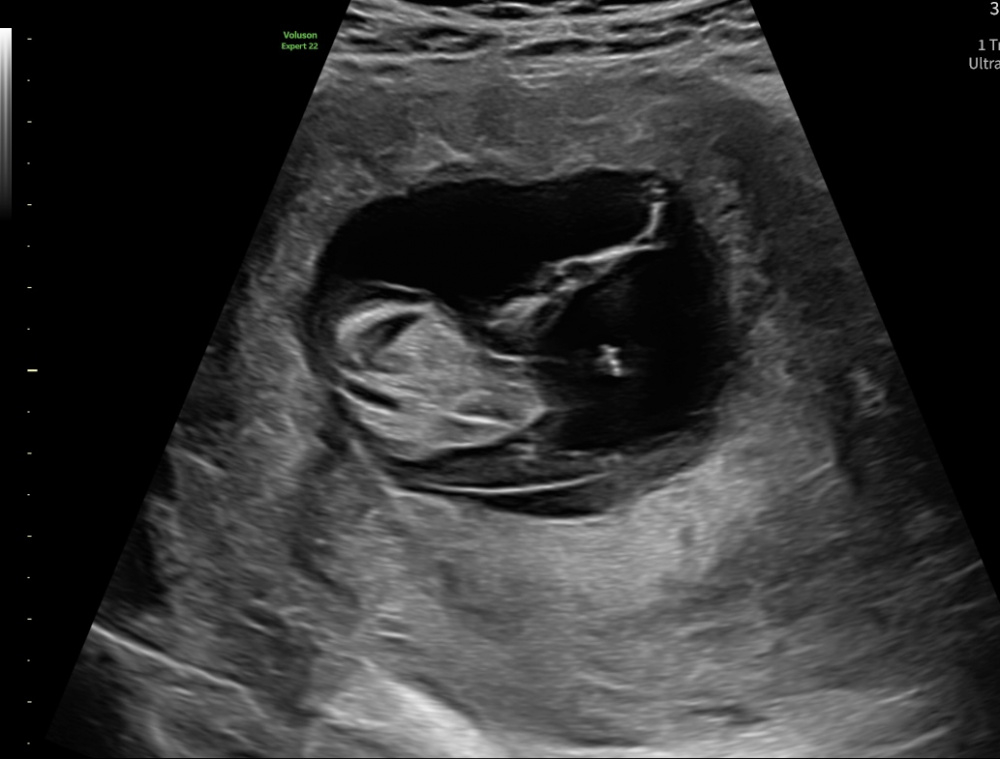

Ich war hier 12+2 der Frauenarzt wollte nichts zum Geschlecht sagen aber ich tendiere eher zum Jungen oder sah es bei einem Mädchen auch so aus in der 13ten Woche?

Nun war ich letzten Montag beim Ersttrimesterscreening. Da war ich 13+1. Die Ärztin meinte am Schluss sie hätte etwas gesehen. Ein Zipfel, ziemlich schmal und spitz. Bei meinem Sohn sah das ganz anders aus. Dennoch sagte sie Tendenz Junge. Ich weiß man soll sich über ein gesundes Kind freuen. Ich weiß dass ich das Kind liebe auch wenn es wieder ein Junge wird. Aber ich bin so traurig und kann seit dem an nichts anderes denken. Nun habe ich viel gelesen und auch hier immer wieder gehört, dass sich Ärzte irren, dass dieser Zipfel auch bei Mädchen vorkommt, usw. Wir haben auch den nipt gemacht. Da steht das Geschlecht aber nicht drin weil das Ergebnis zu früh war(muss ja mindestens Ende ssw 14 sein). Das heißt ganz sicher weiß ich es immer noch nicht und wollte nun mal eure erfahrenen Augen drauf schauen lassen... Was seht ihr auf den Bildern? Das eine ist von 6+1,die anderen vom Screening letzte Woche. Was ist eure Einschätzung? Kann mir jemand Hoffnung machen, dass die Tendenz falsch ist? Hatte jemand schon mal eine falsche Tendenz in der Woche? Bitte helft mir!

@Mondmama921 Also beim Nub ist immer ein Zipfel zu sehen. Das ist ja eben der Nub, sowohl bei Mädchen als auch Bub. Allerdings kann ich die auf deinen Ultraschallbildern nicht ausmachen, um da eine Tendenz sagen zu können. Ich sehe auf dem letzten Bild zwar etwas, was der Nub sein könnte, aber dafür ist’s mir etwas zu ungenau. Hat die Ärztin denn angegeben, wie sicher sie sich ist?

Bei uns sieht es so aus und ich bin wirklich über jeden Tipp dankbar. Was denkt ihr? Leider wollte sich das Mäuschen nicht drehen also schaut ihr sozusagen von oben auf das Baby. Team 🩷 oder Team 🩵?